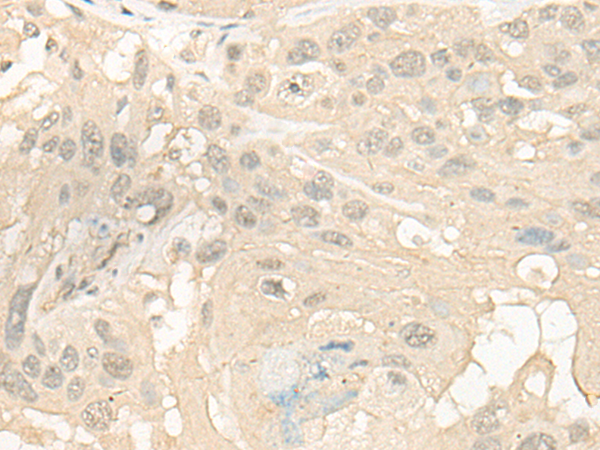

WB (Western Blot)

(Western blot analysis of extracts from 293 cells using Cytochrome P450 4X1 antibody.The lane on the left is treated with the antigen-specific peptide.)